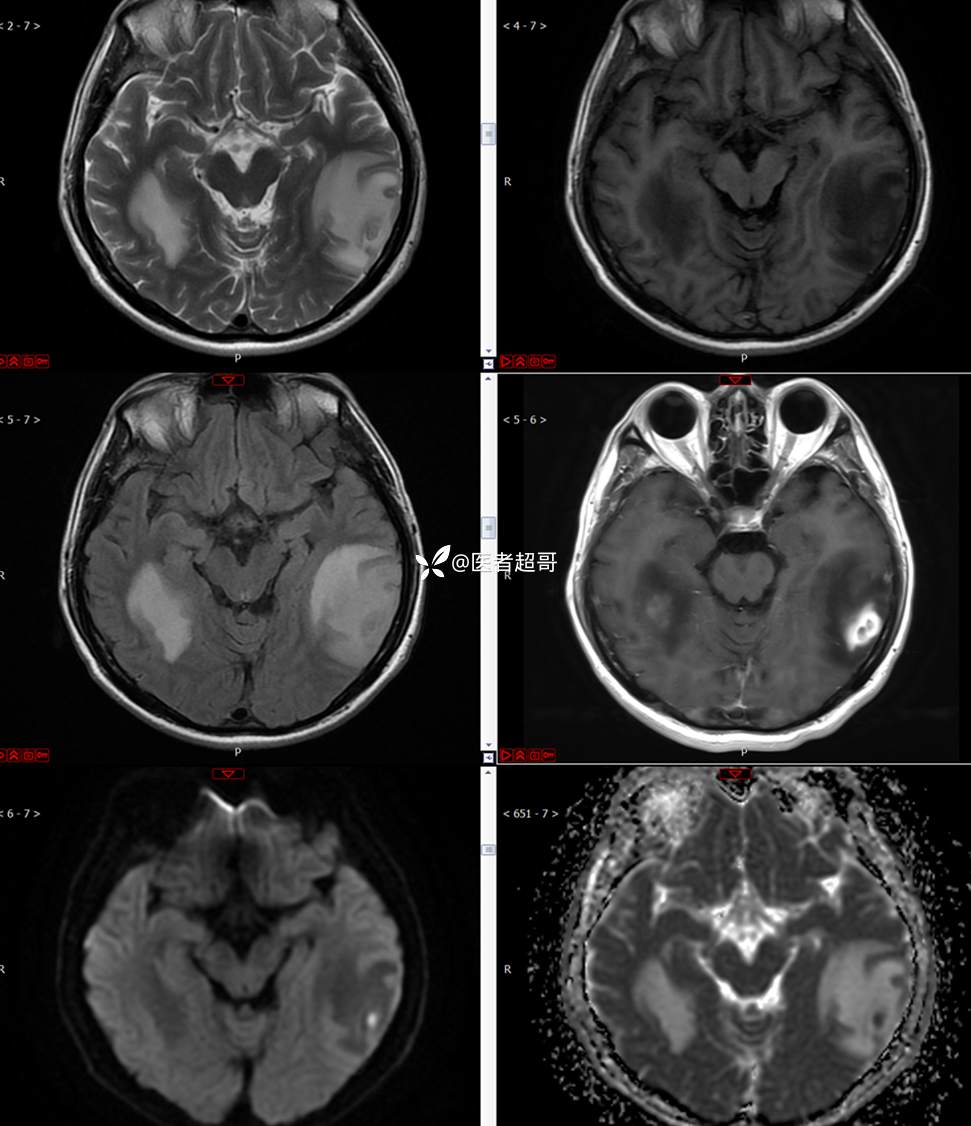

【影诊笔记773】头痛、头晕10天,CT、MRI齐全,请高诊!

主 诉:头痛、头晕10天

现病史:患者10天前无明显诱因感头痛、头晕,伴记忆力减退,无恶心、呕吐,无肢体抽搐及肢体活动不灵等,于我院就诊,行颅脑MR示颅内多发占位,现患者为求进一步治疗于我院就诊,以“颅内占位”收入我科。患者目前神志清,精神可,饮食、睡眠正常,体重无明显变化。

既往史:既往急性肝功能衰竭病史.